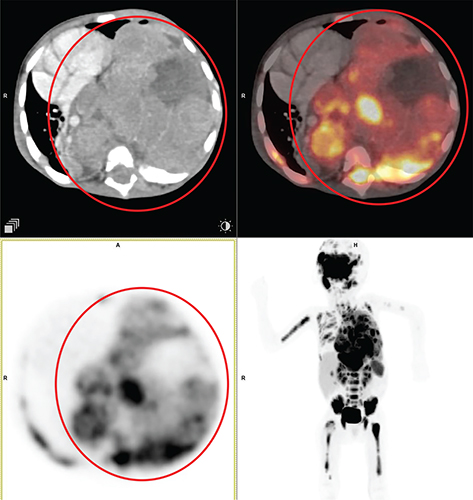

Aggressive thymic epithelial tumors frequently invade or extrinsically compress the superior vena cava (SVC), causing SVC syndrome. Thymic carcinomas typically exhibit more irregular contours, heterogeneity related to hemorrhage, necrosis, and cystic change, as well as higher levels of local vascular and mediastinal invasion and lymphadenopathy (3032). An example of thymic carcinoma is shown in Figure 2.

Fig 2

Figure 2. Thymic carcinoma. Anterior mediastinal mass that was pathologically confirmed as thymic carcinoma. FDG PET/CT images include axial CT (top left panel), fused axial PET/CT (top right panel), axial PET (bottom left panel), and maximum intensity projection (MIP) PET image (bottom right panel). In the red circle, there is a soft tissue density mass with irregular nodular contour showing heterogenous enhancement in CT with heterogenous FDG uptake on PET. There is loss of intervening fat plane with the body of sternum anteriorly and the pulmonary trunk posteriorly concerning for infiltration. There was additional mild to moderately FDG-avid regional lymph nodes and pleural deposits (not on the included PET/CT images and could be appreciated on the MIP image) that were suggestive of metastatic disease.